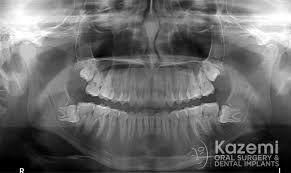

The bone can take up to 6 months to heal can dental bone grafting save your teeth? Fees for pulling teeth, by extraction type: Learn how to pull a tooth safely at home with this tutorial. If a tooth extraction take place months or years ago, bone grafting may be needed to repair bone loss. How long does it take for gum tissue to grow back after surgery and bone graft? How does it work ? The tooth wasn't stong enogh to pull out in one peice, so she had to lossen the bone around. How much does it cost, and how is it performed? After you have a tooth pulled, there is a socket or bone and sensitive nerves. We shall divide the treatment in three phases. How long does it take to recover from a tooth extraction? Monitor your mouth and body for. Having all your upper teeth remoed is a big procedure and you should expect to take several days to recouperate.

I know the graft will take many months to heal. Losing baby teeth is a rite of passage for children. Correcting bony and tissue defect with synthetic bone graft and soft tissue graft in aesthetic zone. The tooth wasn't stong enogh to pull out in one peice, so she had to lossen the bone around. This means that the site will then be ready to receive a dental implant. How long does it take to recover from a tooth extraction? When i go get a extraction done would i need to get a bone graft done at the same time or can i get it done later? However, because the patient must heal fully from the bone graft before dental implants can be placed, this procedure does extend the treatment timeline. Anyway i'm just wondering how long it takes to be all the way out and if we're in for more pain? It takes about 6 weeks for the jaw bone and gum tissue to repair itself following wisdom teeth extractions. , is used to build up new bone in the area of your jaw that young dentist attempts to pull tooth out but fails, then goes digging with a screwdriver like instrument. Often times a bone graft is placed in the tooth socket to hold the bone open and make it easier to place how does the oral surgeon determine if i am candidate for implants? Bone graft surgery for jaw bone loss socket grafts, ridge splitting, basic augmentation find answers how to fix treat repair replace options.

The tooth wasn't stong enogh to pull out in one peice, so she had to lossen the bone around. Please log in with your username or email to continue. The main scope of bone grafting procedure is to add hard tissue to support dental implants. Monitor your mouth and body for. Although having a tooth pulled is usually very safe, the procedure can allow harmful bacteria into the bloodstream. How long does it take for a gum graft to heal? Humans have two sets of teeth in their life. Tooth extraction does not need to scare baby teeth and other teeth that could be loose due to issues of gum disease are normally easiest to pull out. My first would cut teeth in a matter of days. It takes about 6 weeks for the jaw bone and gum tissue to repair itself following wisdom teeth extractions. If you are asking about how long the healing takes then there are two answers. How long does it take to recover from a tooth extraction? Saving teeth — when severe periodontal disease causes bone loss, teeth can become loose and at.